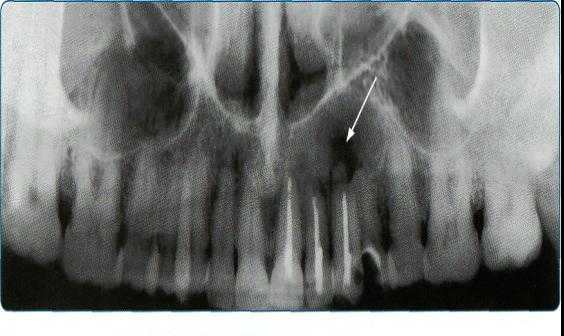

Подбородочно-носовую проекцию применяют для исследования верхней челюсти, верхнечелюстных пазух, полости носа, лобной кости, глазницы, скуловых костей и скуловых дуг.

На рентгенограммах лицевого черепа в лобно-носовой проекции видны верхняя и нижняя челюсти, на них проецируются кости основания черепа и шейные позвонки.

Рентгенограмму черепа в передней аксиальной проекции выполняют для оценки стенок верхнече¬люстной пазухи, в том числе задней, полости носа, скуловых костей и дуг; на ней видна нижняя челюсть в аксиальной проекции.